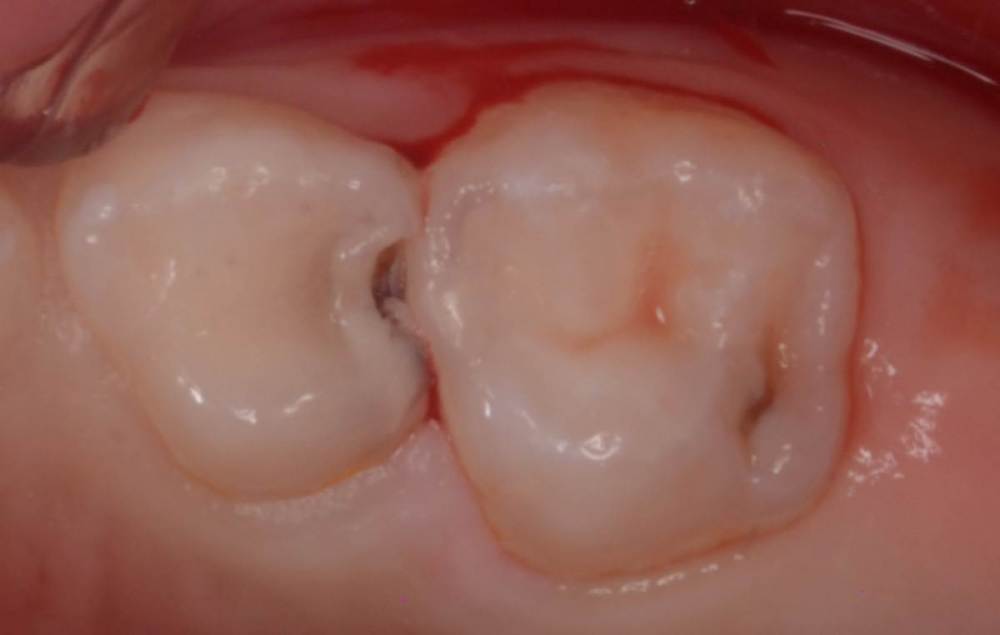

CRAZYDUCK Опубликовано 26 июня, 2022 Автор Поделиться Опубликовано 26 июня, 2022 Гипоминерализация . Границы препарирования … Будет ли разрушаться изменённая в цвете эмаль ? Этот вопрос остаётся открытым . Все , что жду от родителей - настаивать на гигиене и контролировать ее у своих детей и не забывать про регулярные осмотры . 3 1 Ссылка на комментарий